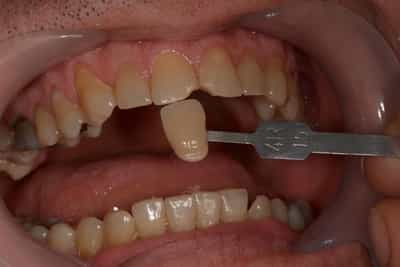

Etude du cas et proposition

Cas terminé